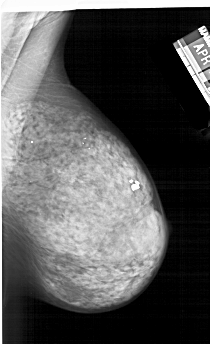

A_1242_1.LEFT_CC

FILE: A_1242_1.LEFT_CC.OVERLAY

TOTAL_ABNORMALITIES 1

ABNORMALITY 1

LESION_TYPE CALCIFICATION TYPE PUNCTATE DISTRIBUTION CLUSTERED

ASSESSMENT 4

SUBTLETY 2

PATHOLOGY BENIGN

TOTAL_OUTLINES 1

BOUNDARY